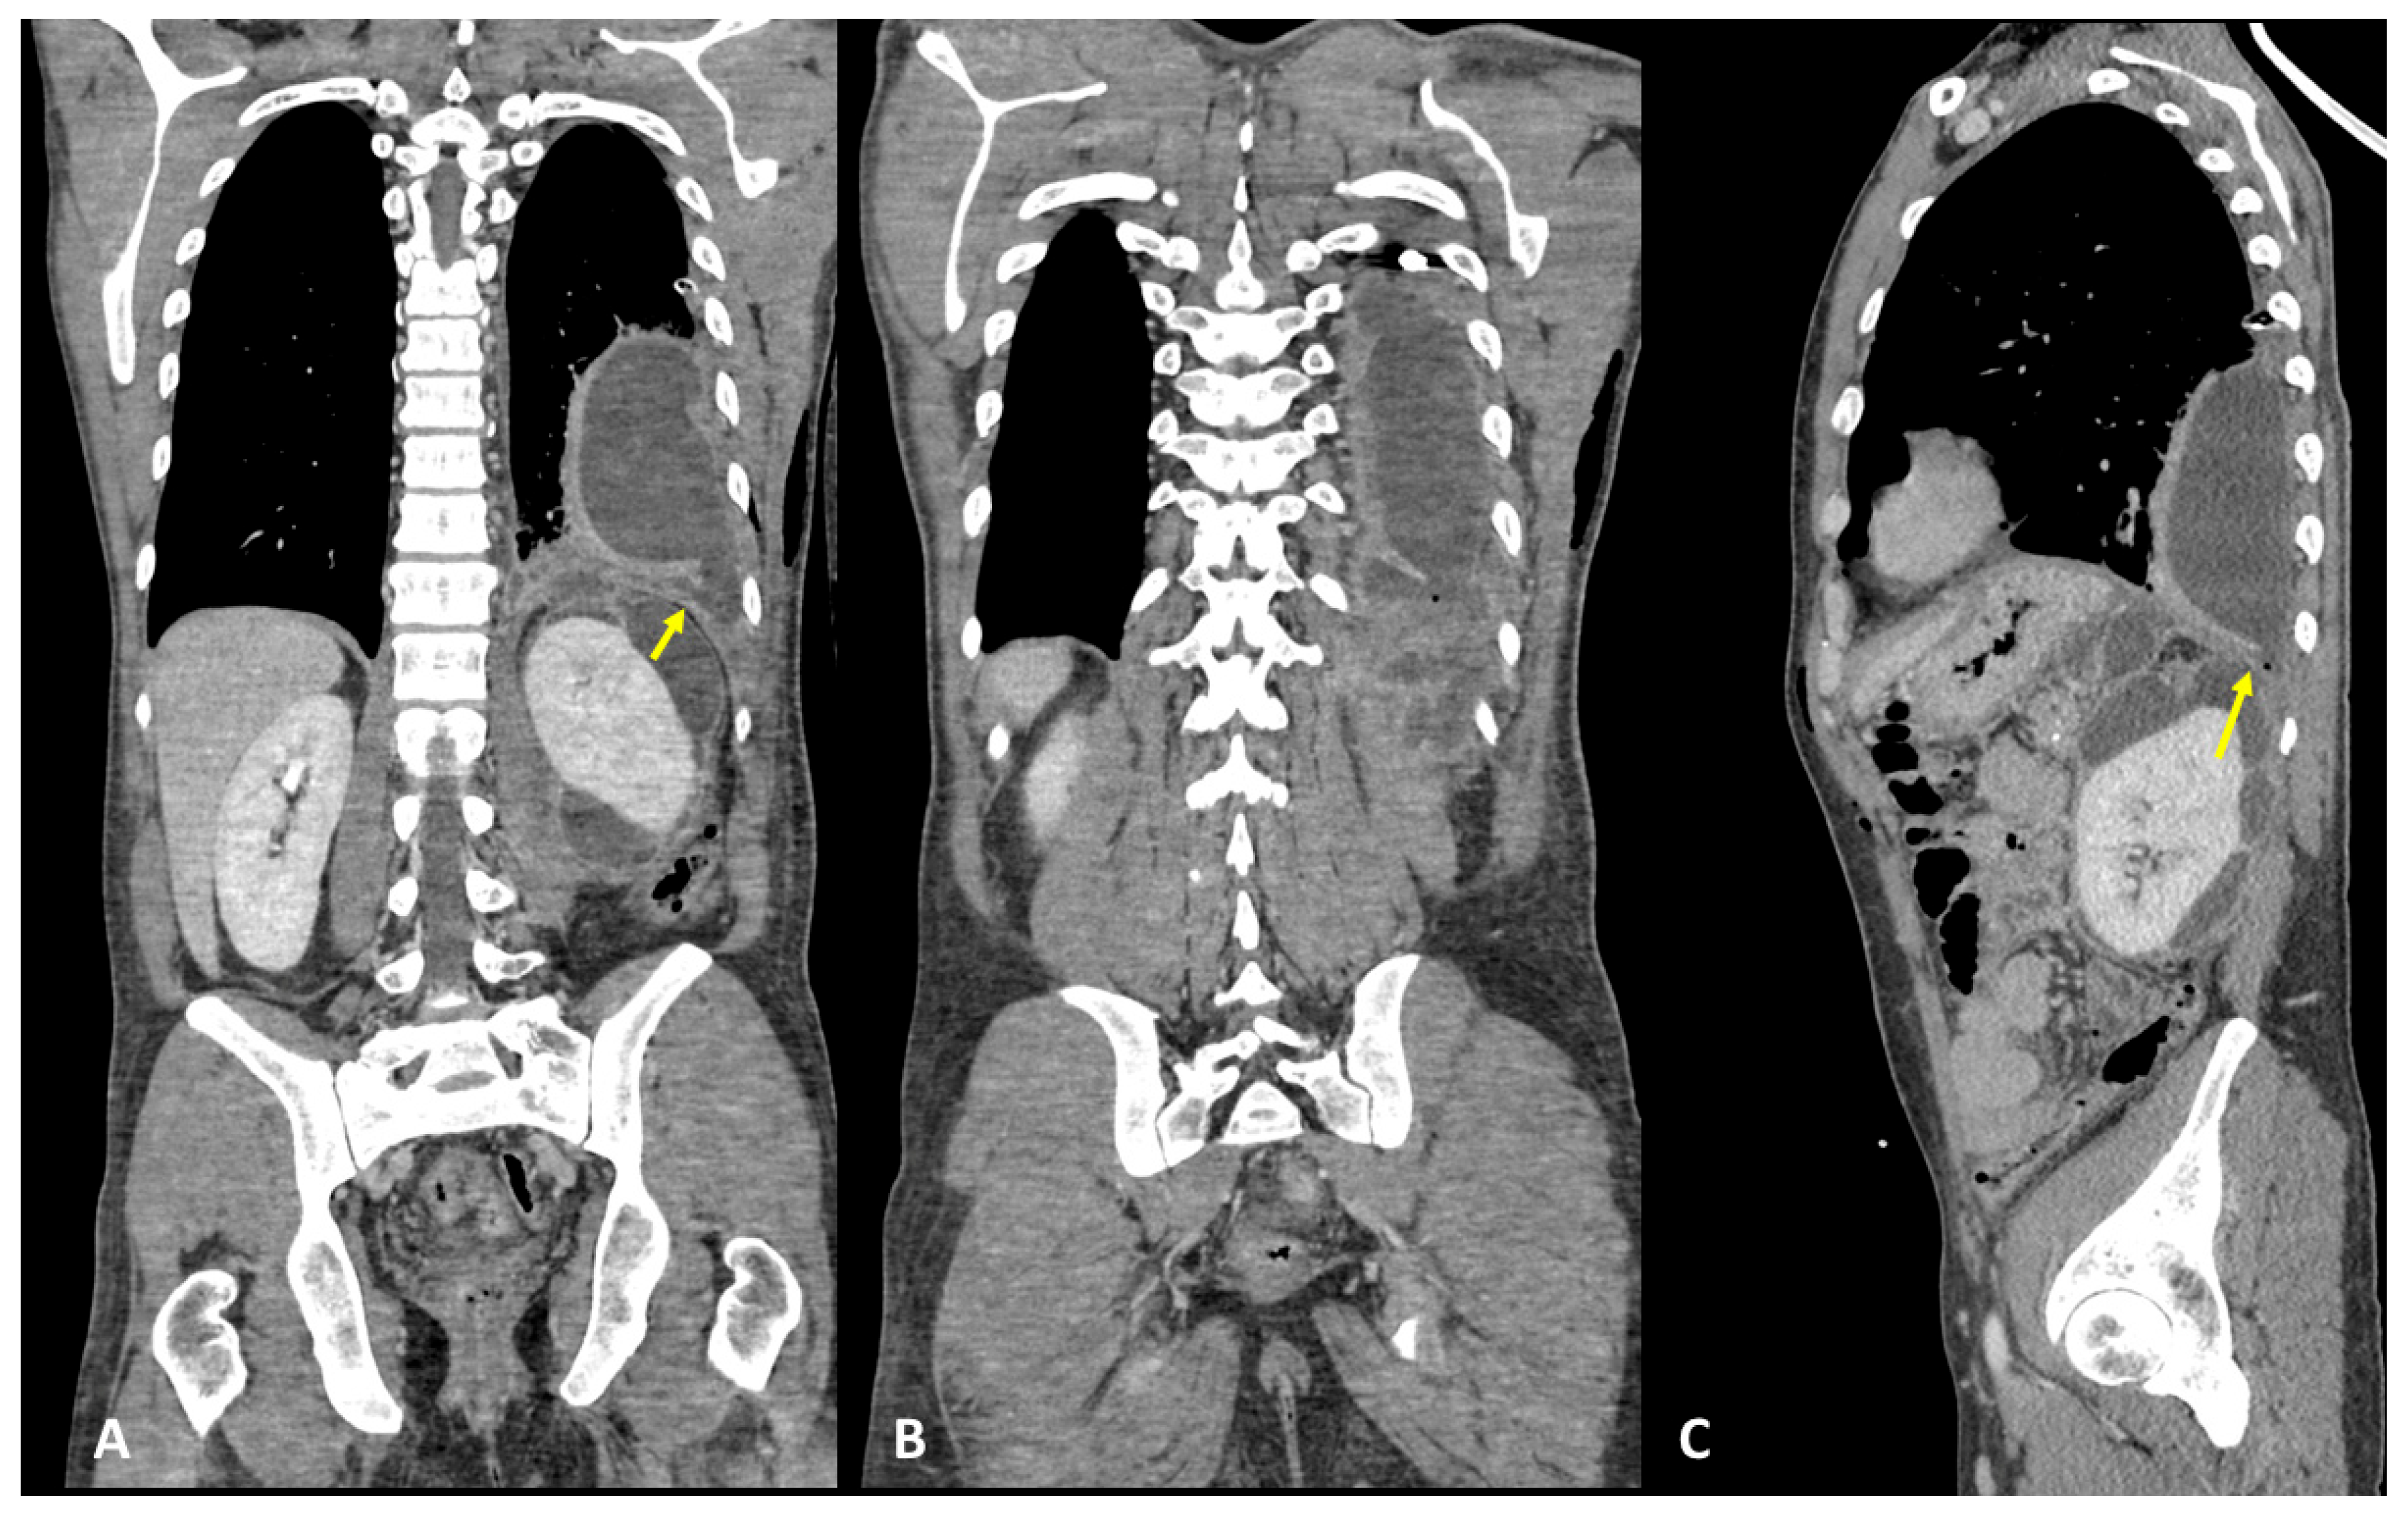

3.4. Case #4: Pancreaticopleural Fistula

4. Results and Discussion